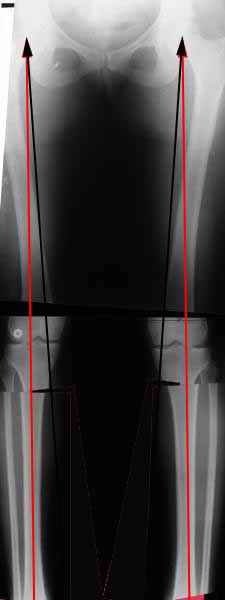

. On the right leg you can see some of the tools (from the tool bar above) applied to demonstrate a mild mech-axis varus of about 5 degrees.

On the left the bone landmarks used in the anlaysis are shown.

The data for the analysis are in the XLs sheet below, exported from the program automatically.

I have given a label of the abreviations and some normative values.

In essence she has a mild mech-axis varus of 7 degrees with some contribution from the femur (2) degrees and more from the tibia (6 degrees), none from the joint.

The analysis took about 6 mins.

TDVC> In essence she has a mild mech-axis varus of 7 degrees

TDVC> with some contribution from the femur (2) degrees and more from

TDVC> the tibia (6 degrees), none from the joint.

And what is conclusion? Should it be corrected, by what means, at what level, to what axis, with what lateral/medial translation?